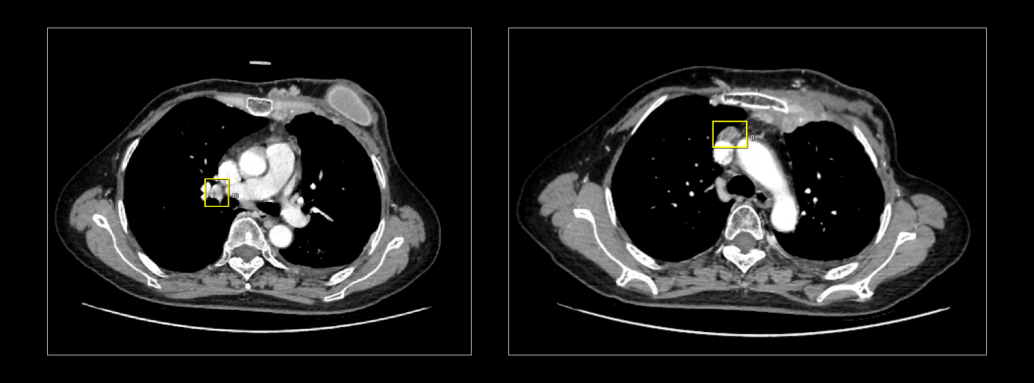

该CT淋巴结AI人工智能分析系统通过AI赋能,精准识别纵隔、腋下的肿大淋巴结及乳腺肿块,并自动进行量化分析。

在此基础上,该CT淋巴结AI人工智能分析系统也依据国际权威图谱实现纵隔淋巴结分区,为医生提供了详细的淋巴结位置信息。